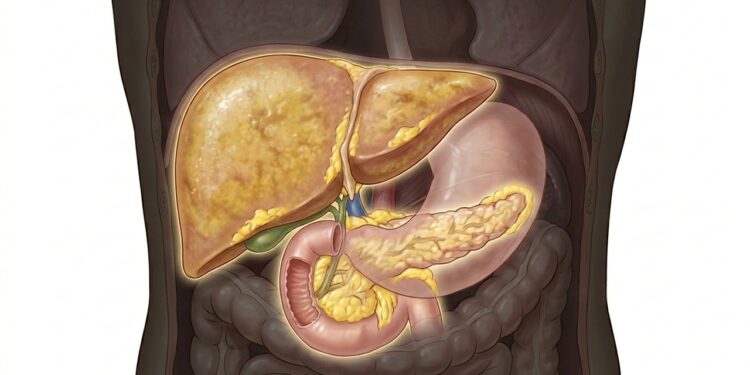

Os cientistas também observaram que a inflamação crônica está ligada a alterações no sistema imunológico e na comunicação entre as células. Esse desequilíbrio pode afetar órgãos importantes, como fígado e músculos, que são essenciais no controle da glicose.